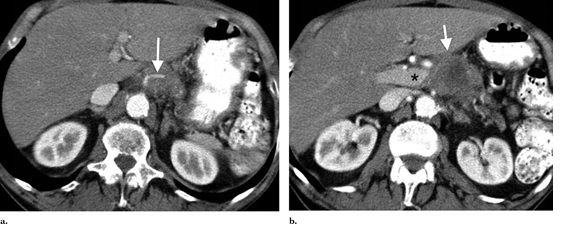

一名76岁的非裔美国男性诊断出患有不可切除胰腺癌III期(肿瘤/瘤/转移阶段)在他拒绝了化疗和射频之后二次血管入侵使得他选择了经皮IRE(纳米刀消融术)技术。CT成像(图表 1)表明4.1X4.1X3,5cm肿瘤包含腹腔动脉,肠系膜上静脉的起源,肝外门静脉堵塞和上肠系膜静脉。全身CT扫描显示没有转移性疾病。

图一:肿块大小:4.1X4.1X3,5cm,肿瘤侵犯了腹腔动脉、肠系膜上静脉、肝外门静脉